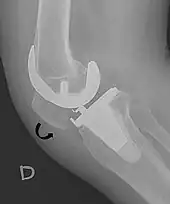

- 1 2 Douglas Dennis (2017-02-25). "TKA in Patella Baja (Infera)". Orthobullets. Retrieved 2019-02-08.